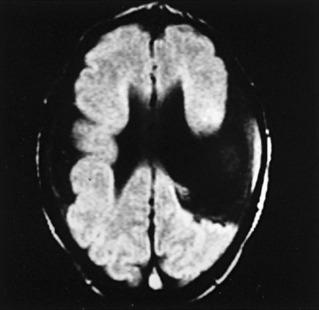

Magnetic resonance imaging (MRI) shows bilateral perisylvian gyral dysgenesis including pachygyria, and polymicrogyria ( Fig. 17.1 ). Postmortem studies have confirmed the MRI impression.

Fig. 17.1, Magnetic Resonance Imaging (MRI) of Congenital Bilateral Perisylvian Syndrome.